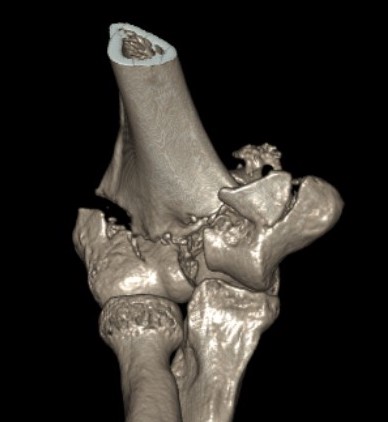

CT scan

Type C: Complete articular fractures

Operative Management

1. ORIF